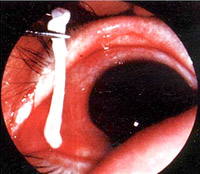

- Bệnh ấu trùng sán nhái ở hệ hô hấp (Pleuropulmonary sparganosis)

Bệnh sán nhái có thể di chuyển gây kích ứng, khiến bệnh nhân ho khan, không có đờm, giống như hội chứng Loffler, gây thương tổn ở màng phổi và nhu mô phổi.

Hình 14. Ấu trùng sán nhái tổn thương ở vùng đỉnh màng phổi qua nội soi ngực

Hình 15. Ấu trùng sán nhái tổn thương và bội nhiễm hóa mủ ở phổi